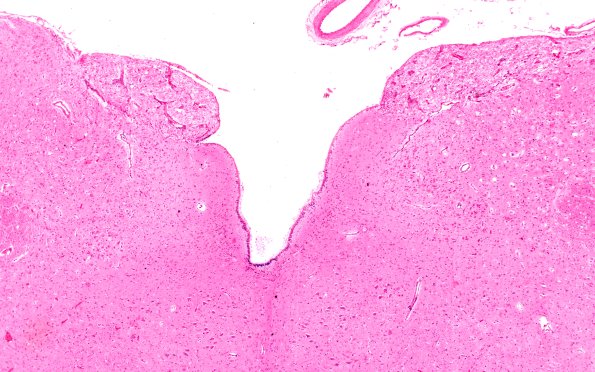

2D1-3 This is a section of medulla in which the area postrema, a site in which the blood brain barrier is absent, shows viral inclusions (arrow, 2D3). (H&E)